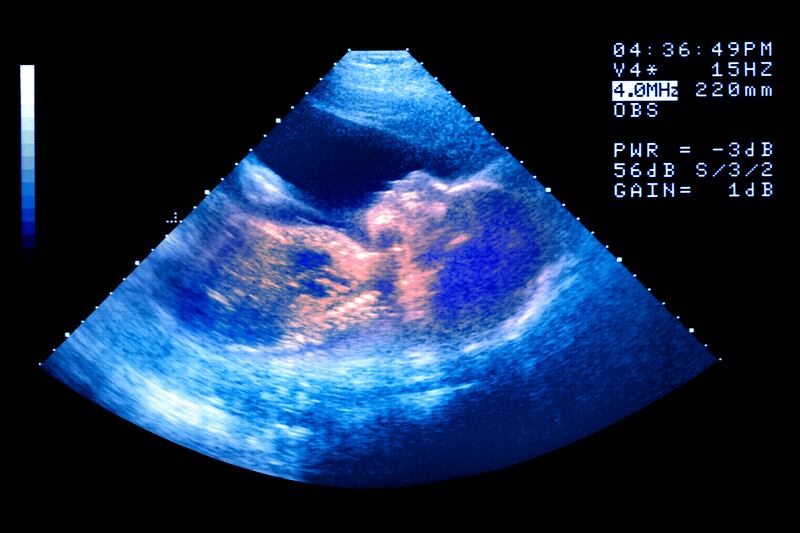

The vast majority of infertile African women can’t get pregnant because of fallopian tubes clogged by infections. That makes them, in one sense, perfect candidates for in vitro fertilization because IVF works best on women who have clogged tubes and no other hormonal issues. Doctors bypass the tubes and place the embryo right in the womb. Skeptics point out that money should be used to prevent infections in the first place.